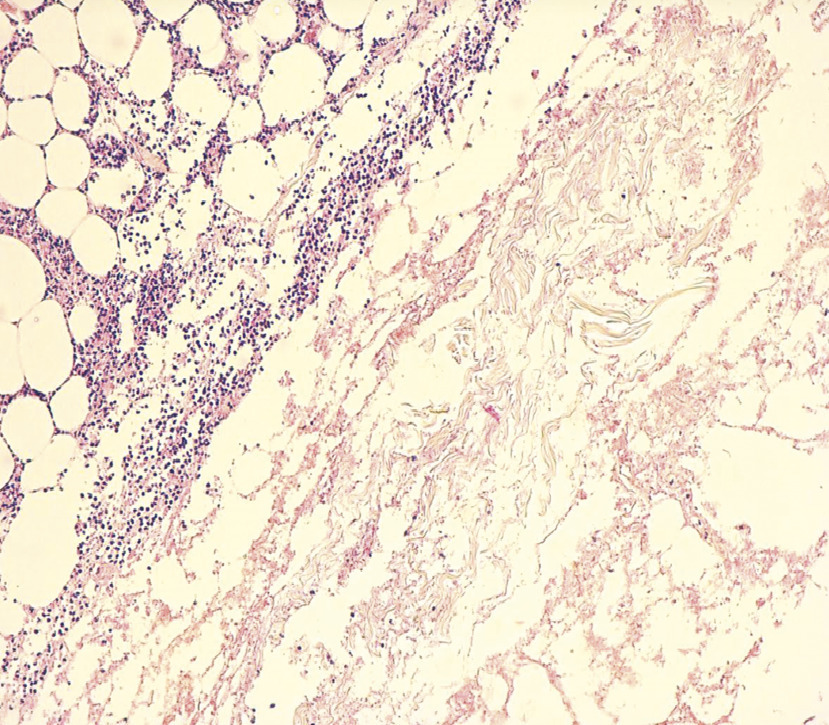

Cette femme de 70 ans, de faible niveau socio-économique, obèse et diabétique de type 2 depuis 20 ans et sous insuline depuis 10 ans, consultait aux urgences pour une douleur de la fosse iliaque gauche. Elle était consciente, tachycarde, fébrile (39,5 °C), et sa glycémie capillaire était à 1,8 g/dL sans cétose. L’examen abdominal notait un placard érythémato-érosif chaud de la fosse iliaque gauche centré par une nécrose bien limitée en carte de géographie (fig. 1 ). La patiente rapportait avoir injecté l’insuline à ce même endroit depuis 3 ans. Le bilan biologique montrait une glycémie à 1,6 g/dL, une hyperleucocytose à 14 500/mm3, une CRP à 130 mg/L et une procalcitonine normale. L’échographie et la tomodensitométrie abdominale montraient un épaississement de la paroi abdominale sans abcès ni collections profondes. Le diagnostic retenu était celui de fasciite nécrosante. Cette patiente était traitée par une antibiothérapie à large spectre avec mise à plat et excision large. L’histologie mettait en évidence des thromboses septiques (fig. 2 ) ainsi qu’une nécrose étendue du derme (fig. 3 ).